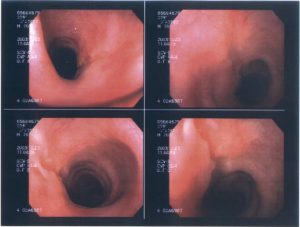

При подозрении на стриктуру пищевода, врач может рекомендовать пациенту провести эзофагоскопию и рентгенологическое исследование с использованием контрастного вещества (сульфата бария). Эндоскопическое исследование позволяет определить место сужения, осмотреть слизистые оболочки пищевода и взять биопсию для гистологического анализа. Это поможет выяснить причину патологии. Однако стоит отметить, что эндоскопия не позволяет видеть пищевод за местом сужения, поэтому рентгенологическое исследование также необходимо. Во время рентгена можно оценить прохождение контрастного вещества через суженное место, анализировать перистальтику органа и состояние внутренних стенок.